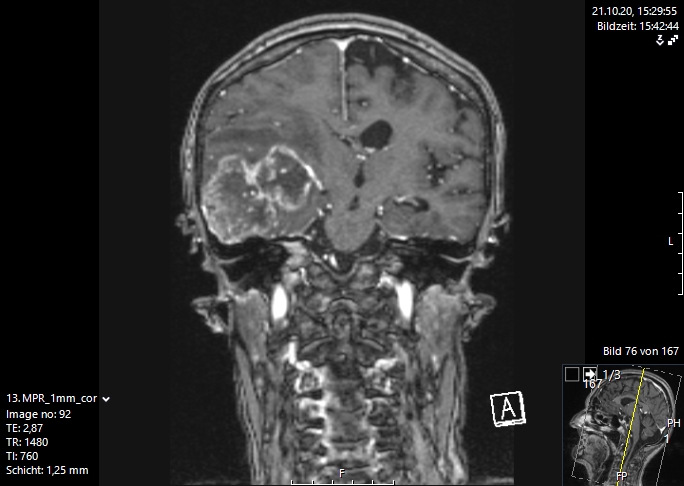

Η μαγνητική τομογραφία εγκεφάλου είναι η μέθοδος εκλογής για την απεικόνιση των εγκεφαλικών μεταστάσεων. Αυτή διενεργείται είτε επί υποψίας αλλοίωσης στο κεντρικό νευρικό σύστημα, λόγω ανάπτυξης μιας νευρολογικής συμπτωματολογίας ή απλά στα πλαίσια του γενικού staging με τακτικές απεικονίσεις στο σώμα και στον εγκέφαλο. Με τη βοήθεια αυτής της απεικονιστικής διαδικασίας μπορεί να γίνει ορατός ο παθολογικά αλλοιωμένος εγκεφαλικός ιστός με τις νεκρώσεις του καθώς και το περιεστιακό εγκεφαλικό οίδημα (συσσώρευση νερού στον εγκέφαλο).

Σήμερα υπάρχουν διάφορες διεγχειρητικές τεχνικές, που μας υποστηρίζουν στο στόχο μας, να αφαιρέσουμε όσο περισσότερο καρκινικό ιστό , αν γίνεται ιστό ακόμα και από την περιοχή γύρω από τον όγκο, που ονομάζουμε διηθητική ζώνη. Μερικές σύγχρονες διεγχειρητικές τεχνικές, είναι η νευροπαρακολούθηση, η νευροπλοήγηση με απεικόνιση των δεσμίδων, η ενδοσκοπική νευροχειρουργική και τα χειρουργεία με ασθενή σε εγρήγορση. Ο συνδυασμός λοιπόν ενός ασφαλούς χειρουργείου με ταυτόχρονη ολική αφαίρεση του όγκου αποτελεί τον στόχο της σύγχρονης χειρουργικής νευρο-ογκολογίας και στην περίπτωση των εγκεφαλικών μεταστάσεων. Οι εικόνες 1 και 2 απεικονίζουν μια ολική εξαίρεση μιας μετάστασης δεξιά κροταφικά. Αυτό είναι σαφέστατα πιο πιθανό να προσφερθεί από ειδήμονες νευροχειρουργούς (Gousias K, 2024) με ειδική εκπαίδευση σε μεγάλα κέντρα, μεγάλη χειρουργική εμπειρία και εξειδίκευση στην χειρουργική των όγκων καθώς και διεθνή αναγνώριση τους. Η επιτροπή Χειρουργικής Νευρο-ογκολογίας της Ευρωπαϊκής Νευροχειρουργικής Εταιρείας δημοσίευσε το προφίλ ενός expert χειρουργού για όγκους εγκεφάλου και νωτιαίου μυελού (Gousias K, 2024).